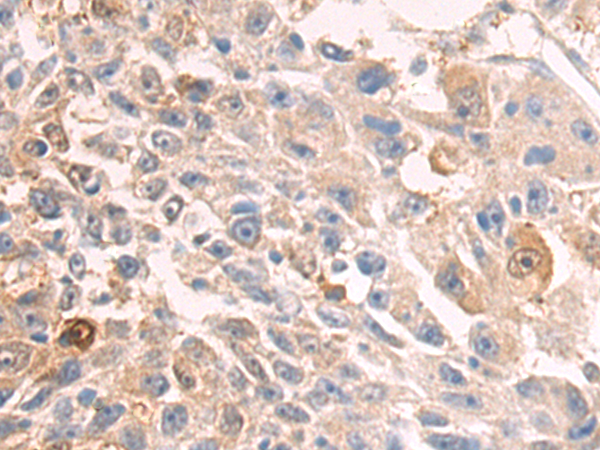

分类: 科研抗体货号: P08286别名: PCPH; CD39L4; NTPDase-5应用: WB,IHC反应种属: Human, Mouse, Rat